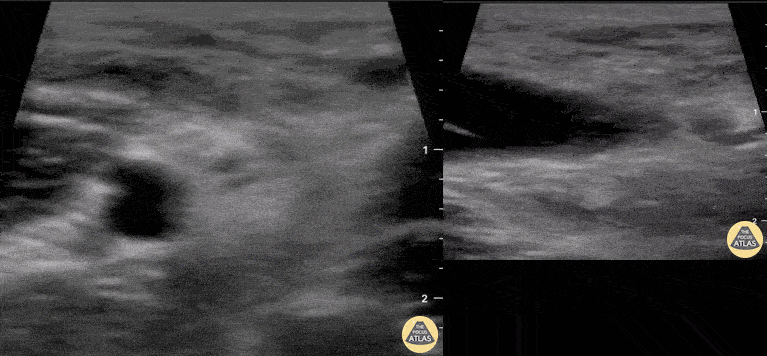

A 30-year-old male presented with acute-onset left anterior elbow pain after feeling a “pop” while weight-lifting. On exam, there was an obvious reverse popeye sign, swelling and mild ecchymosis. There was slight weakness in flexion and supination. Hook test was positive. A Butterfly IQ was used on an MSK soft tissue setting to assess the tendon in long and short axis via an anterior approach. Discontinuity of the tendon and surrounding anechoic fluid representing hematoma were noted. Orthopaedic surgery was consulted and reviewed ultrasound images. As a result, the patient had an urgent MRI and underwent expedited surgical repair. Melanie Leclerc, MD CCFP(EM). @MelanieLecler19 David Lewis MB,BS FRCS FCEM CFEU PGDipSEM Saint John Regional Hospital, New Brunswick, Canada